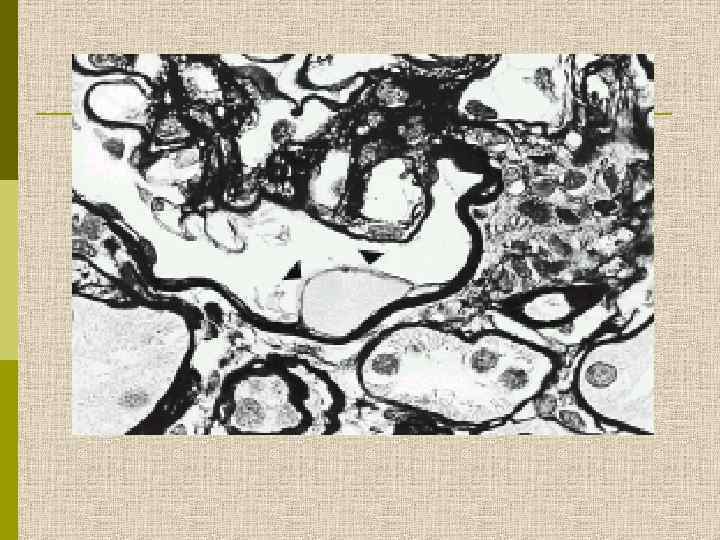

МОРФОЛОГИЧЕСКИЕ ИЗМЕНЕНИЯ ПРИ ДИАБЕТИЧЕСКОЙ НЕФРОПАТИИ Основные варианты - диабетический гломерулосклероз с узелками Kimmelstiel-Wilson - диффузный мезангиальный гломерулосклероз Характерные признаки Утолщение ГБМ; артериолярный гиалиноз; аневризматические капилляры; капсулярные капли; фибриновые шапочки; атрофия канальцев; инфильтрация, расширение и склероз интерстиция; линейные отложения иммуноглобулинов

Диабетическая микроангиопатия/утолщение базальной мембраны 1. Образование аневризм 2. Утолщение базальной мембраны 3. Leakyсосуды и базальные мембраны